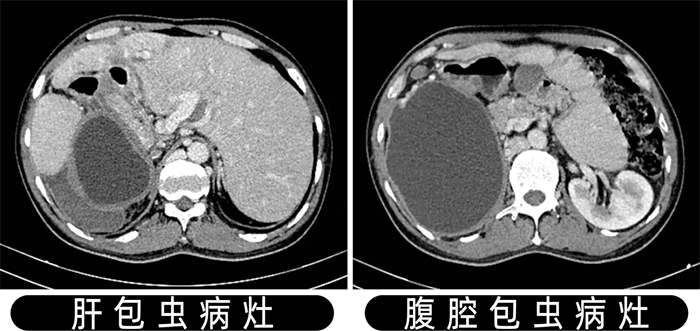

患者是一名中年男性,因“反复腹痛1月”住院于肝胆外科,经腹部CT、彩超检查提示:肝脏多发包虫病灶及腹腔巨大包虫病灶。

我院肝胆外科杨闯主任医疗团队对患者的病情进行了充分评估,认为患者有手术指征,但患者的肝脏包虫病灶较大且多发合并腹腔巨大包虫,包虫病灶波及重要血管和邻近器官,手术难度大。

本次手术,杨闯医疗团队借助数字化三维成像技术,充分展示了肝脏包虫病灶、腹腔包虫病灶与重要组织器官的关系,成功精准实施肝脏及腹腔包虫病手术,这标志着我院肝胆外科对肝包虫病的治疗跨上新台阶。